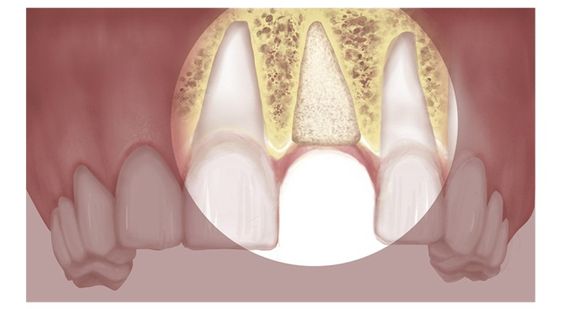

تشخیص آنکیلوز دندان از طریق ترکیبی از معاینه بالینی و تکنیک های تصویربرداری پیشرفته تشخیص داده می شود. در طول ارزیابی بالینی، متخصصین دندانپزشکی قوس دندانی بیمار را بازرسی می کنند و موقعیت، تحرک و تراز دندان را ارزیابی می کنند. با این حال، مشخصه آنکیلوزدندان عدم تحرک طبیعی آن است. برای تایید تشخیص و ارزیابی میزان آنکیلوز، از ابزارهای تصویربرداری پیشرفته مانند توموگرافی کامپیوتری با پرتو مخروطی (CBCT) استفاده میشود. عکس CBCT تصاویر سه بعدی از دندان ها و ساختارهای اطراف را ارائه می دهد و رابطه پیچیده بین دندان انکیلوز و استخوان مجاور دندان را آشکار می کند. این تصاویر دقیق به تعیین شدت آنکیلوز کمک می کند، که برای برنامه ریزی استراتژی های درمانی مناسب حیاتی است.

آنکیلوز دندان اغلب با ویژگی های بالینی مشخص ظاهر می شود. برجسته ترین علامت دندان فک جوش عدم تحرک طبیعی دندان است، زیرا دندان ذوب شده توانایی حرکت در حفره خود را ندارد.دندان فک جوش می تواند منجر به تراز نامناسب و انسداد دندان های مجاور شود. در برخی موارد، آنکیلوز دندان ممکن است منجر به تغییرات قابل توجهی در ظاهر ناحیه آسیب دیده شود، مانند کوتاهتر ظاهر شدن دندان یا عدم رویش کامل دندان؛ در مواردی نیز دیده شده است، به دلیل اینکه دندان انکیلوز شده رویش نمییابد، تعداد دندانهای بیمار از یک فرد عادی کمتر خواهد بود و نیروی کمتری به دندانهای فک مقابل وارد میشود. به همین دلیل هم دندانهای فک مقابل ممکن است کمی بیرونتر از حالت معمول دیده شوند.

علاوه بر این، دندانهای انکیلوز ممکن است به نیروهای ارتودنسی که برای حرکت دادن آنها در نظر گرفته شدهاند پاسخ ندهند و این وضعیت را بیشتر تایید میکند. با این حال، توجه به این نکته مهم است که انکیلوز ممکن است همیشه با علائم قابل توجه همراه نباشد و تشخیص آن معمولاً به ارزیابی جامع توسط متخصص دندانپزشکی، به ویژه از طریق تکنیکهای تصویربرداری مانند CBCT، برای شناسایی دقیق حضور و تأثیر آن نیاز دارد.